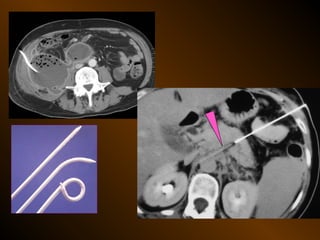

X QUANG CAN THIỆP

Dẫn lưu áp xe bụng

Thủ thuật nghẽn mạch cầm máu

Dẫn lưu đường mật

Mở túi mật ra da

TỤ KHÍ NGOÀI PHÚC MẠC

• Nguyên nhân :

– Thủng tạng rỗng

– Áp xe tạo khí

• X quang quy ước

• Siêu âm

• XQCLĐT

TỤ KHÍ NGOÀIPHÚC MẠC • Nguyên nhân : – Thủng tạng rỗng – Áp xe tạo khí • X quang quy ước • Siêu âm • XQCLĐT